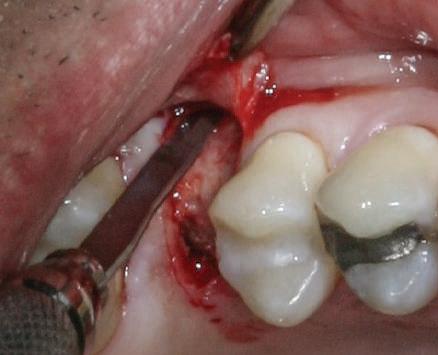

Cazul (3)

Refrezarea bonturilor individualizate

Pacientul prezenta dentiţie maxilară şi mandibulară eşuată datorită cariei secundare provocată de xerostomia post-iradiere. Pacientul suferise o disecţie cervicală radicală pentru înlăturarea carcinomului cu celule scuamoase la nivelul gâtului cu 9 ani înainte, urmată de radioterapie dar fără limită de ecranare. S-a utilizat o abordare stadializată pentru a evita protezele mobilizabile pe ţesuturile moi, extrem de uscate. Pacientul a optat pentru tratarea prioritară la nivel mandibular.

Fig. 9 prezintă bonturile de vindecare adiacente dinţilor naturali menţinuţi temporar, iar fig. 10 bonturile individualizate din prima etapă, inserate cu un contur gingival relativ bun şi fără recesie. Recesia era clar vizibilă în jurul tuturor bonturilor din prima etapă, după extracţiile adiacente şi plasarea implanturilor din a doua etapă (fig. 11). Atitudine: S-a decis îndepărtarea acestor bonturi şi amprenta corpului implantar al tuturor implanturilor astfel încât bonturile noi şi cele din prima etapă să fie frezate împreună pentru paralelism şi poziţionarea adecvată a marginii gingivale. Întrucât aceasta necesita îndepărtarea bonturilor din prima etapă care menţineau proteza provizorie, înainte de îndepărtarea tuturor bonturilor individualizate s-au plasat bonturi provizorii, cu scopul de a asigura poziţionarea adecvată şi dimensiunea verticală a restaurării provizorii. Aceste bonturi provizorii au menţinut apoi restaurarea temporară,

Cazul (3): Refrezarea bonturilor individualizate

Figurile

9. Bonturile de vindecare.

10. Bonturile individualizate în prima etapă.

11. Recesia evidentă în jurul bonturilor din prima etapă, după extracţiile adiacente şi inserarea implanturilor din faza a doua.

12. Bonturile refrezate şi noile bonturi individualizate.

în timp ce toate bonturile individualizate au fost fabricate şi/sau frezate în laborator. Fig. 12 prezintă plasarea bonturilor refrezate (la implanturile din prima etapă) şi bonturile individualizate noi (la cele din a doua etapă).